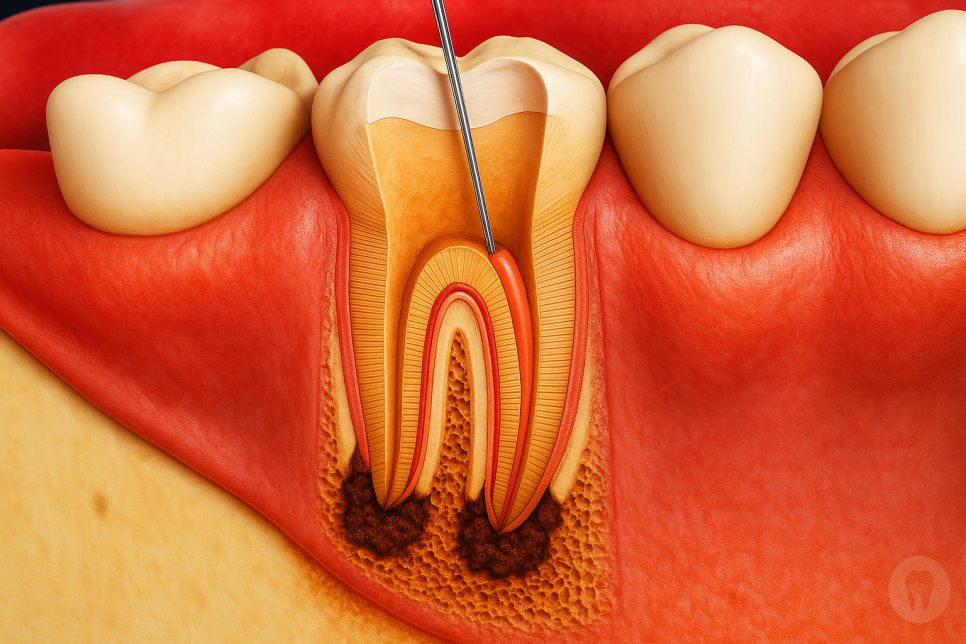

먼저 치관 속에는 하나의 관이 아니라

주근관 축근관 부근관과 협부를 비롯한

여러 구성 요소들을 갖고 있습니다.

또한 그 모양도 사람마다 조금씩

다르게 형성되어 있습니다.

그렇다 보니 경우에 따라서는

복잡한 구조로 인해 일반 도구로는

접근할 수 없는 부분이 생기고,

이곳에 잔존하는 세균으로 인해

전 처럼 통증이 올 수 있습니다.